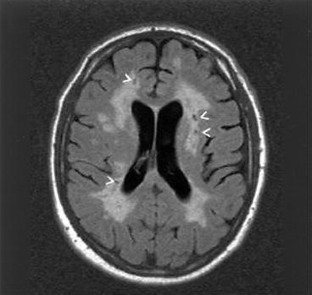

Fig. 1.